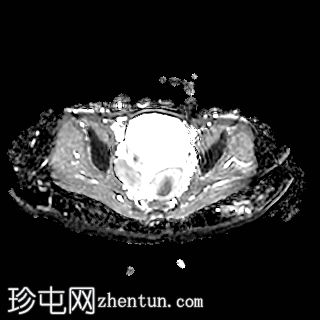

轴位

T1加权像

右侧卵巢增大,卵泡呈周边排列。

附件血管蒂扭转(漩涡征)。

右侧附件旁可见一较大的、边界清晰的盆腔囊性病变,向右倾斜,提示为卵巢旁囊肿。

本病例展示了卵巢扭转的典型影像学特征,包括卵巢增大、卵泡呈周边移位、卵巢向内侧偏移以及特征性的漩涡征。

在这种情况下,较大的卵巢旁囊肿被认为是发生卵巢扭转的高危因素。如果卵巢旁囊肿较大(>5厘米)或活动度较大,其重量/活动度增加会牵拉附件,导致卵巢和输卵管发生扭转。